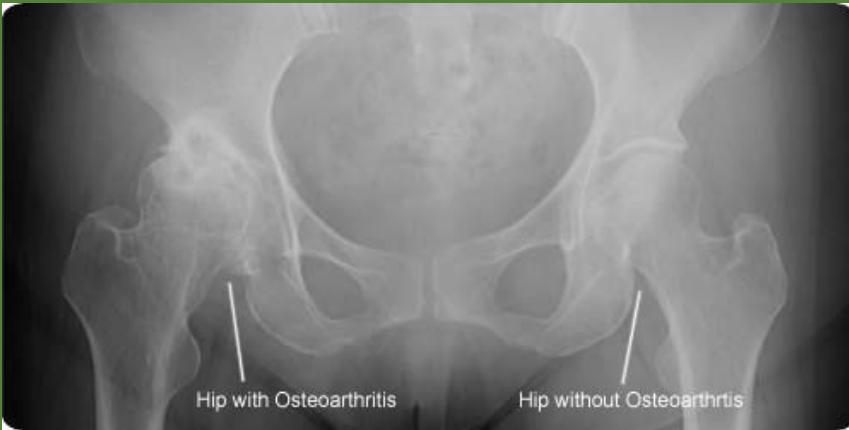

Station 3: Hip Examination

Hip Examination